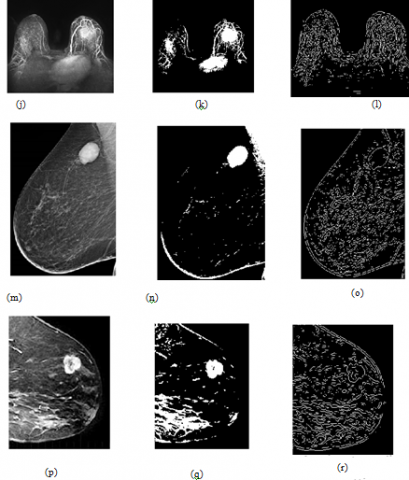

The data flow process for classification system is shown in Figure 7. The Figures 8, 9, 10 and 11 represents the tumor analysis based on input image.

Figure 13 shows the MIAS dataset grayscale images converted to binary and the images acquired using my proposed approach.

Figure 13. Tumor prediction